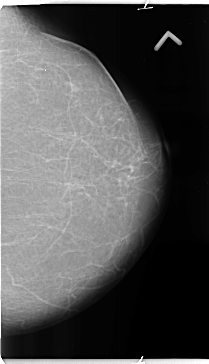

B_3135_1.LEFT_MLO

LEFT_MLO LINES 4752 PIXELS_PER_LINE 2872 BITS_PER_PIXEL 12 RESOLUTION 50 NON_OVERLAY

FILE: B_3135_1.RIGHT_CC.OVERLAY

TOTAL_ABNORMALITIES 2

ABNORMALITY 1

LESION_TYPE MASS SHAPE IRREGULAR MARGINS SPICULATED

ASSESSMENT 4

SUBTLETY 5

PATHOLOGY MALIGNANT

TOTAL_OUTLINES 1

BOUNDARY

ABNORMALITY 2

LESION_TYPE MASS SHAPE IRREGULAR MARGINS ILL_DEFINED

SUBTLETY 4

PATHOLOGY UNPROVEN